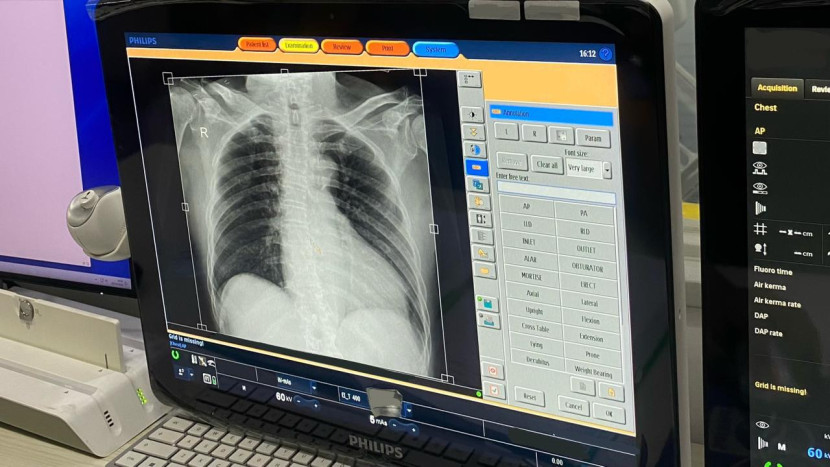

Satu hari mengamati radiografer memberikan pemahaman yang jelas tentang ritme pekerjaan mereka. Aktivitas dimulai dengan menyiapkan ruangan dan alat radiologi. Radiografer secara teliti memastikan kondisi alat agar berfungsi dengan baik. Langkah berikutnya adalah persiapan pasien. Radiografer menjelaskan kepada pasien tentang prosedur pemeriksaan dan memastikan posisi pasien tepat untuk mendapatkan hasil citra yang terbaik.Proses pengambilan gambar dilakukan dengan berbagai alat radiologi, seperti sinar-X, CT scan, dan MRI.

Radiografer mengoperasikan alat dengan hati-hati dan memperhatikan dosis radiasi yang diterima oleh pasien. Setelah pengambilan gambar selesai, radiografer melakukan pemeriksaan awal terhadap kualitas citra.Salah satu hal menarik yang terlihat adalah komunikasi radiografer dengan pasien. Mereka tidak hanya berfungsi sebagai operator alat, tetapi juga sebagai komunikator yang efektif.